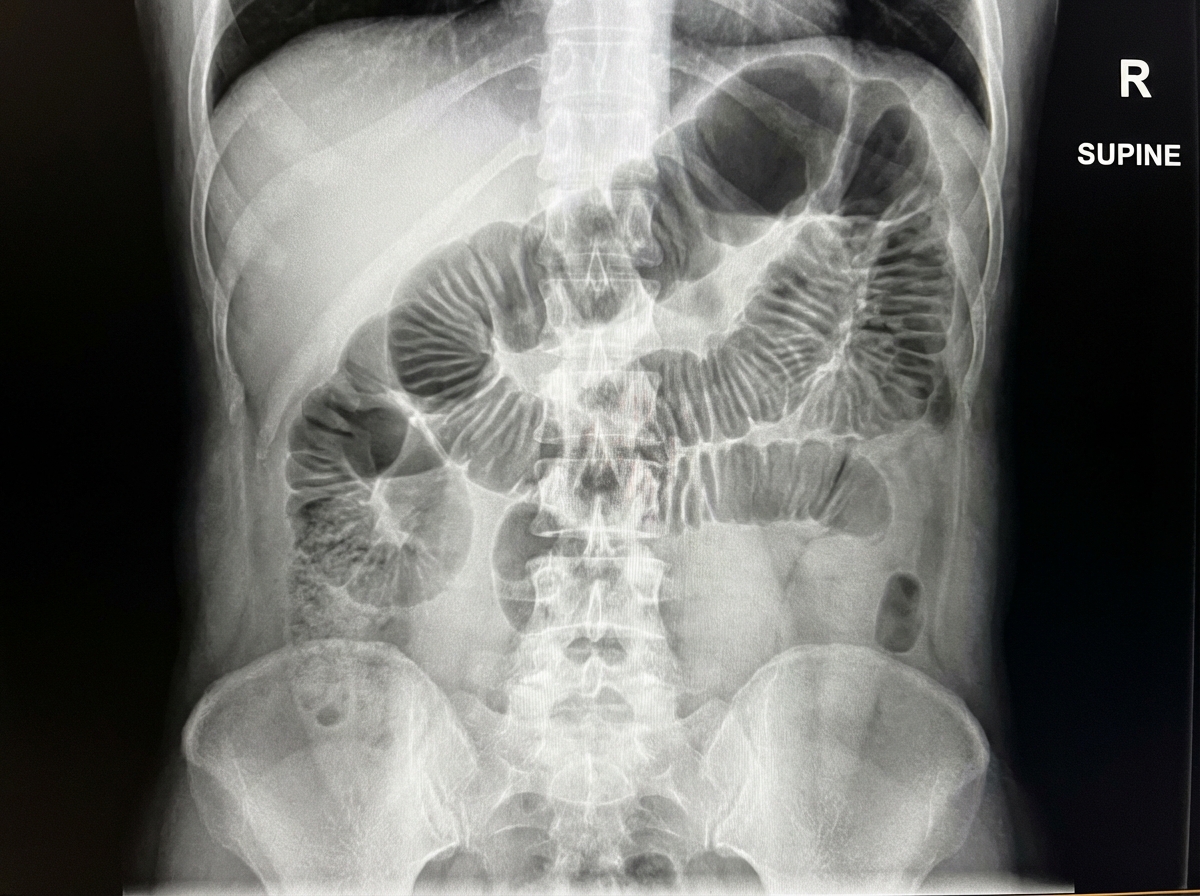

The X-ray demonstrates which of the following conditions?

Explanation: ***Small bowel obstruction*** - Classic X-ray findings include **dilated central loops** with **valvulae conniventes** (complete mucosal folds crossing the bowel) and a **step-ladder pattern**. - Typically shows **absent or minimal large bowel gas** distal to the obstruction point. *Sigmoid volvulus* - Characterized by the pathognomonic **coffee-bean sign** - a massively dilated sigmoid loop resembling a coffee bean shape. - Shows **loss of haustral markings** in the twisted sigmoid segment with a characteristic bent appearance. *Large bowel obstruction* - Demonstrates **dilated peripheral loops** with **haustral markings** (incomplete mucosal folds that don't cross the entire bowel width). - Shows **distended colon** with haustra creating a scalloped appearance, typically sparing the small bowel. *Perforation* - Key finding is **free air under the diaphragm** (pneumoperitoneum) on upright chest X-ray or **Rigler's sign** on supine films. - May show **air outlining both sides** of the bowel wall or air in abnormal locations like the liver edge.